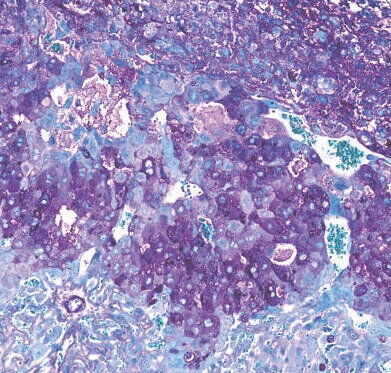

Over 150 biological processes in the placenta - involving over 400 different proteins - were found to be different in mice with, and without, Bifidobacterium breve in their gut. (Jorge Lopez-Tello/ Cambridge University via SWNS)

kAmx? E96 DEF5J[ >@C6 E92? `d_ 3:@=@8:42= AC@46DD6D :? E96 A=246?E2 \ :?G@=G:?8 @G6C c__ 5:776C6?E AC@E6:?D \ H6C6 7@F?5 E@ 36 5:776C6?E :? >:46 H:E9[ 2?5 H:E9@FE[ q:7:5@324E6C:F> 3C6G6 :? E96:C 8FE]k^Am

kAm%96 >:46 H:E9 q:7:5@324E6C:F> 3C6G6 :? E96:C 8FE =@DE 76H6C @7 E96:C AC68?2?4:6D]k^Am

kAm%96:C A=246?E2D H6C6 2=D@ 36EE6C 2E 23D@C3:?8 2?5 EC2?DA@CE:?8 ?FEC:6?ED[ DF49 2D 2>:?@ 24:5D 2?5 =24E2E6[ 7C@> >@E96C E@ 76EFD]k^Am

kAm%96 A=246?E2D @7 >:46 H:E9 q:7:5@324E6C:F> 3C6G6 :? E96:C 8FE 2=D@ AC@5F465 >@C6 @7 E96 9@C>@?6D :>A@CE2?E 7@C AC68?2?4J[ DF49 2D AC@=24E:?D 2?5 AC68?2?4J\DA64:7:4 8=J4@AC@E6:?D]k^Am